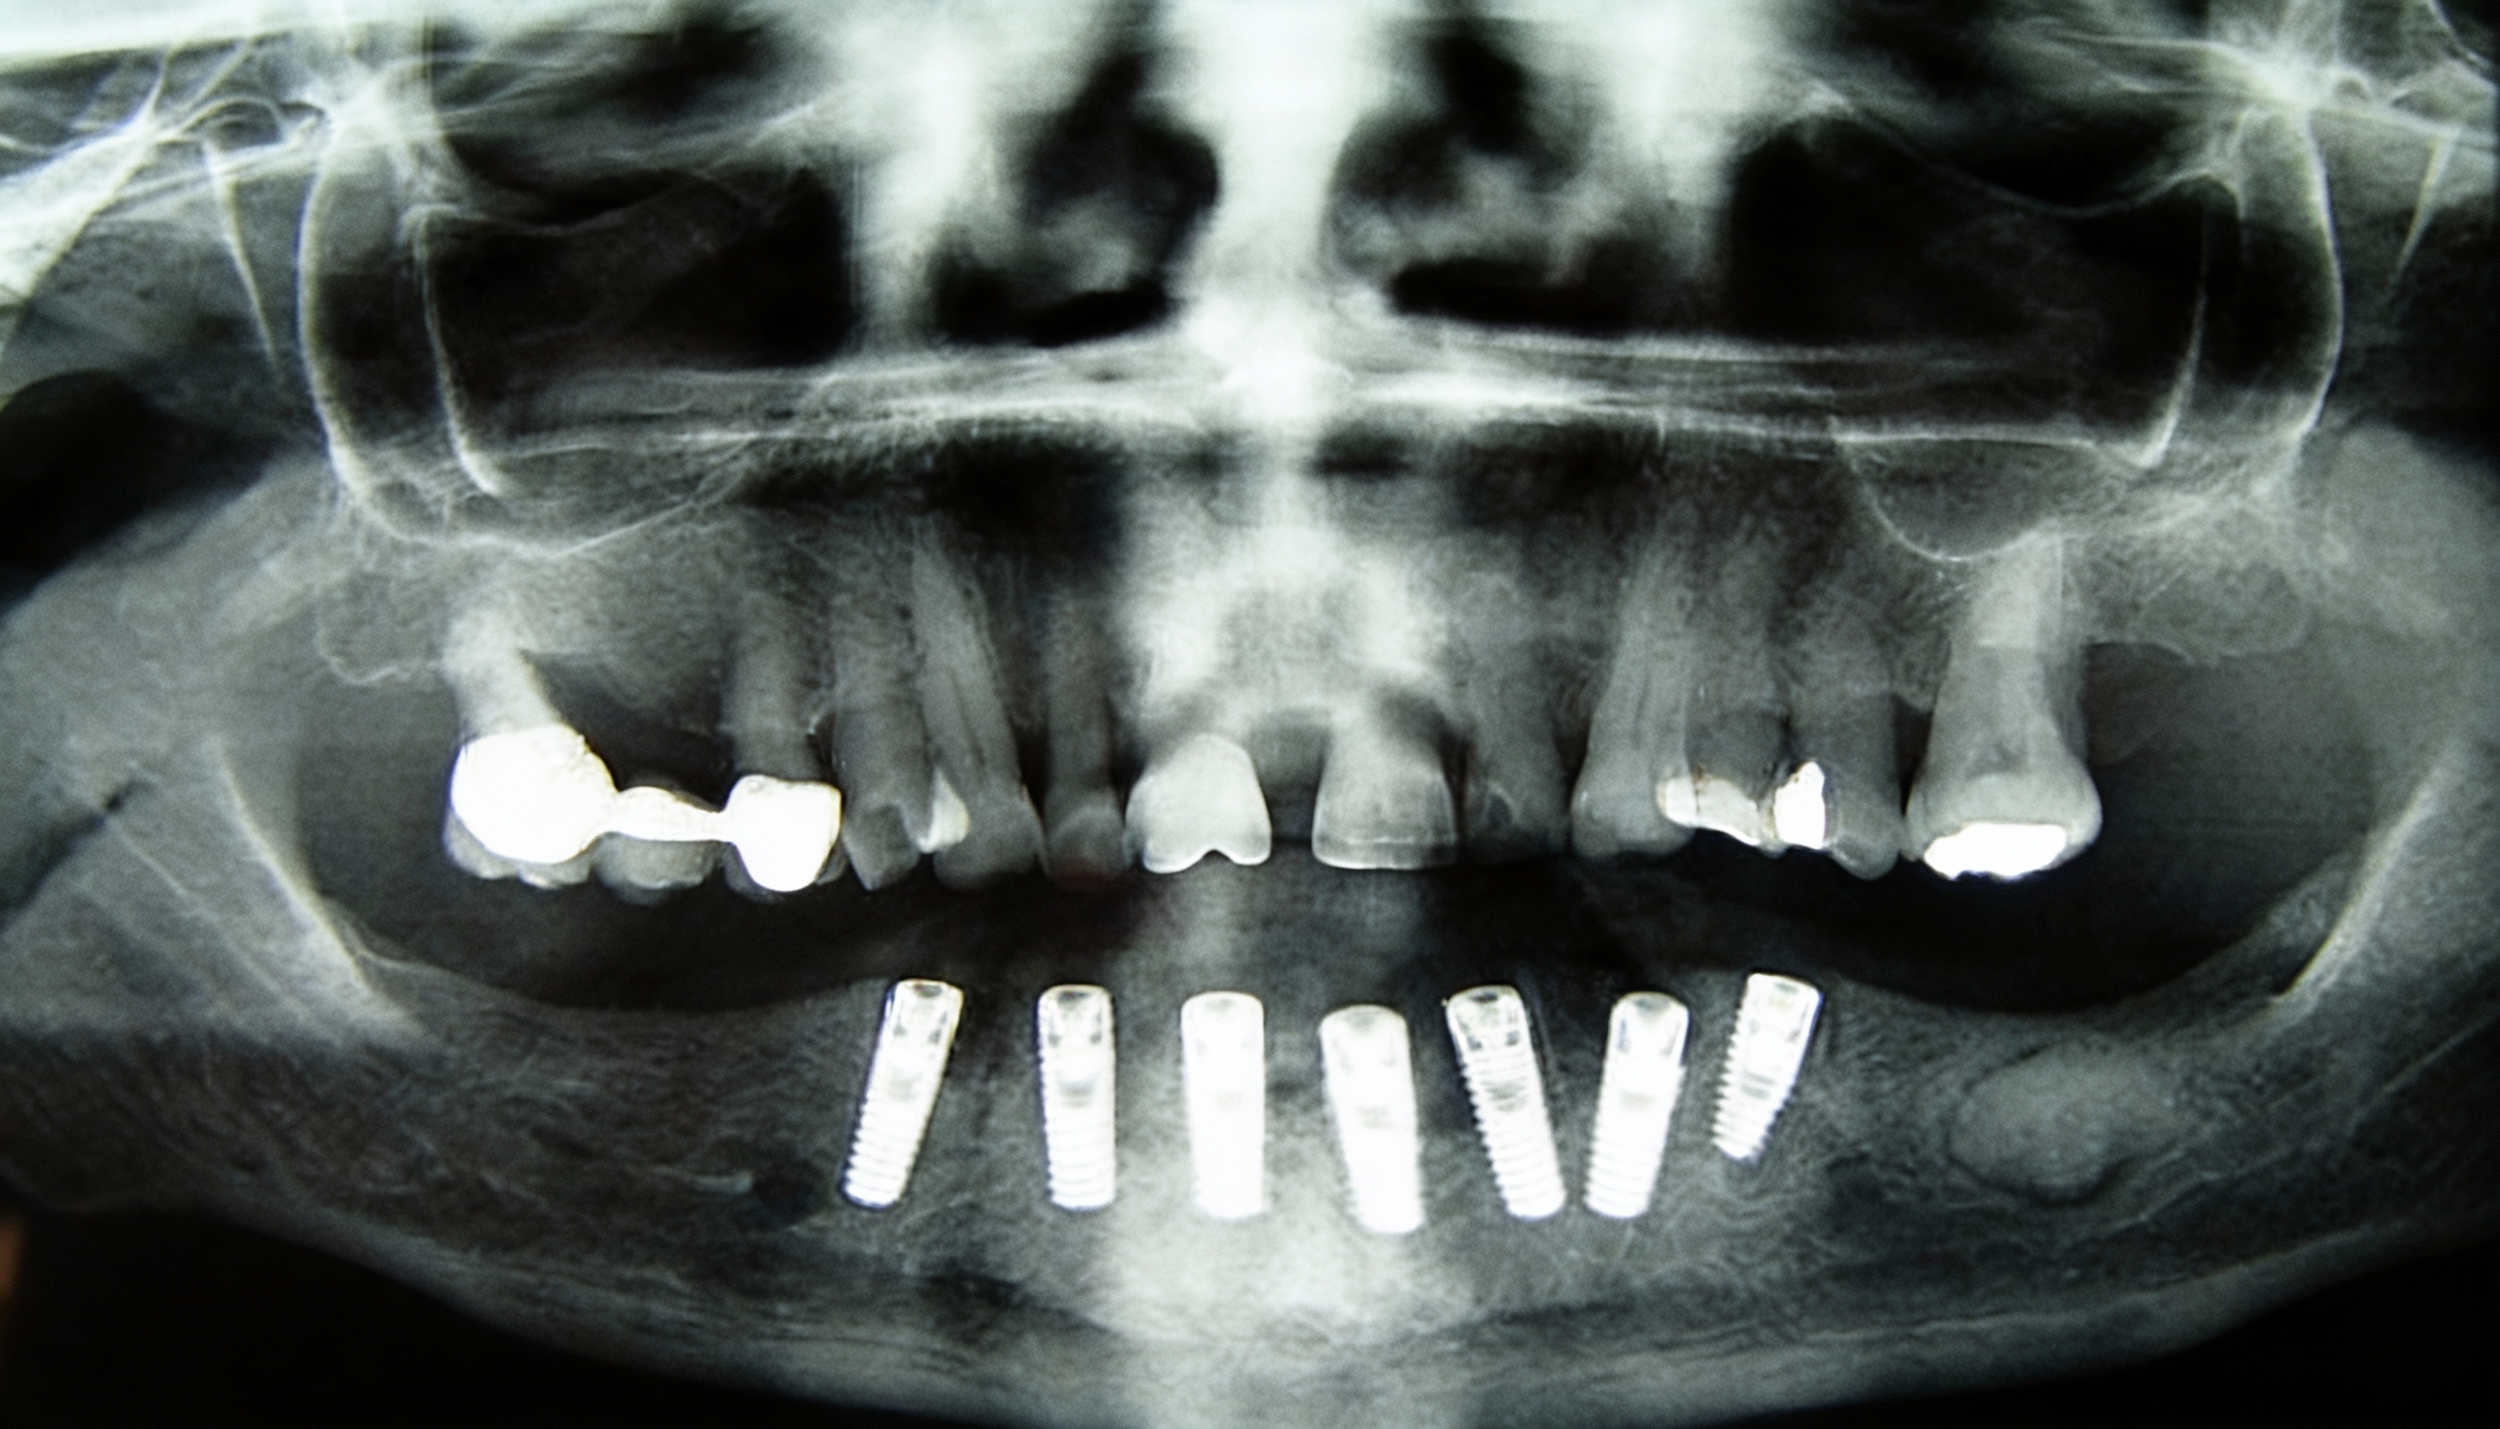

Major Bone Augmentation

For extensive ridge defects, our biomaterials deliver both scaffold support and biological. performance: horizontal & vertical ridge reconstruction, severe atrophy cases before implant placement, combined GBR with membrane stabilisation.

Benefits: Cortical strength for space maintenance, cancellous porosity for cell ingrowth, compatible with tenting screws, meshes or sausage-technique.